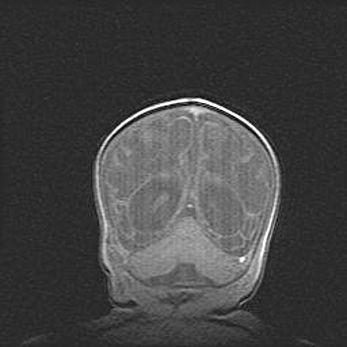

Открытая гидроцефалия.

Возраст: 9 месяцев 12 дней

Вес: 6800 г

Пол: мужской

Окружность головы: 41,5 см

Срок гестации: 28 недель

Гидроцефалия головного мозга у новорожденных имеет характерный признак: опережающий рост окружности головы приводит к визуально хорошо определяемой гидроцефальной форме сильно увеличенного в объёме черепа. Детские неврологи определяют следующие симптомы гидроцефалии у грудничков: выбухающий напряжённый родничок, частое запрокидывание головы, смещение глазных яблок к низу.